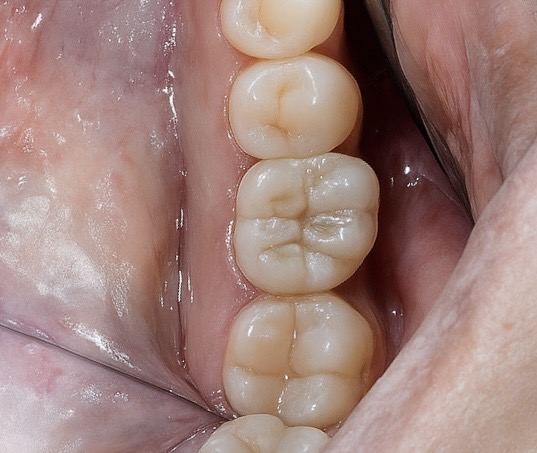

Clinical inspection revealed healthy peri-implant mucosa with an ideal emergence channel and a symmetrical gingival cuff. The tissue tone indicated stable integration of the Swiss implant platform.

- Peri-implant tissues: Firm and pink, with full papillary fill.

6️⃣ Final prosthesis in situ at six months